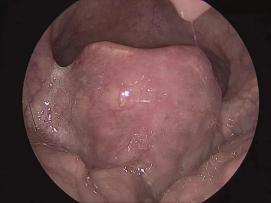

会厌是喉咙前部和舌头之间的叶子状结构,由会厌软骨和粘膜组成。说话或呼吸时,会厌倦向上打开喉咙;吞咽东西时,会厌倦遮住喉咙入口,避免食物进入喉咙。舌面粘膜组织松散,感染时会严重肿胀。

急性厌炎是耳鼻喉科的急危重症之一,是一种特殊的急性炎症病变,主要涉及周围组织。当你厌倦高度肿胀时,可能会引起明显的气道梗塞甚至窒息,这是一种危险而严重的疾病。